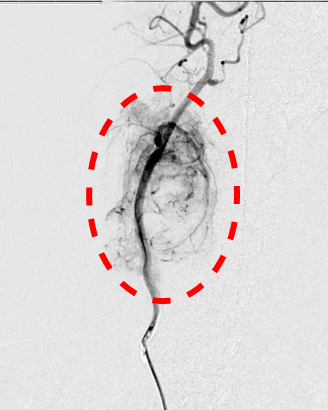

【実施症例】骨盤腔腫瘍に対する動注療法

雑種犬, 11歳, 雄。

摘出手術後に再発した肛門周囲腺癌。腫瘍は骨盤腔内まで浸潤し、再度の外科的切除は困難であった。 左総頸動脈からカテーテルを左内腸骨動脈まで挿入し、腫瘍陰影を確認。抗がん剤および塞栓剤を注入した。 実施後、腫瘍は1/4以下に縮小し正常な排便が維持できている。

骨盤腔のX線透視像

腫瘍陰影

実施前

実施後